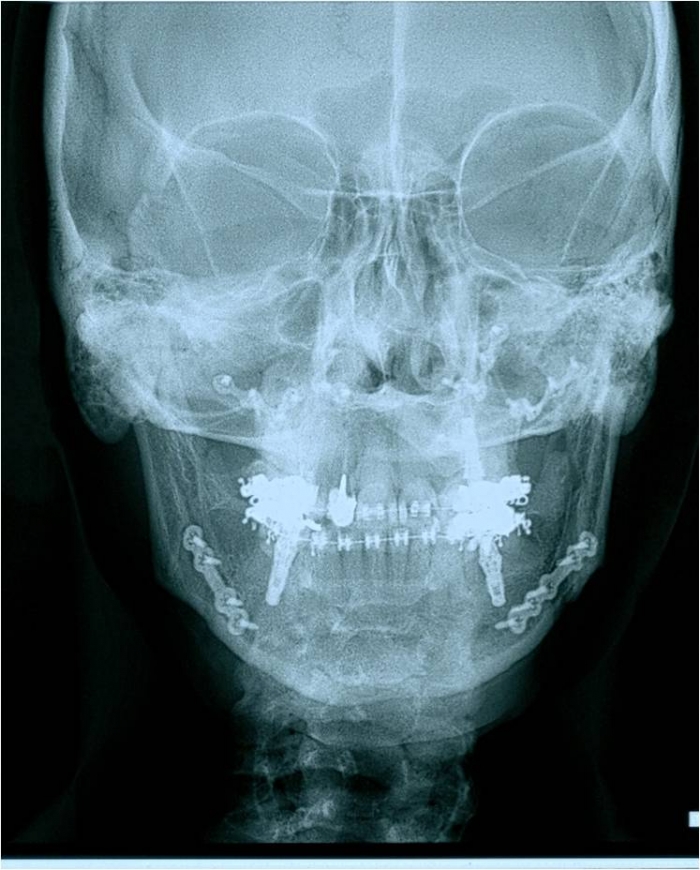

Telerradiografia frontal após a cirurgia